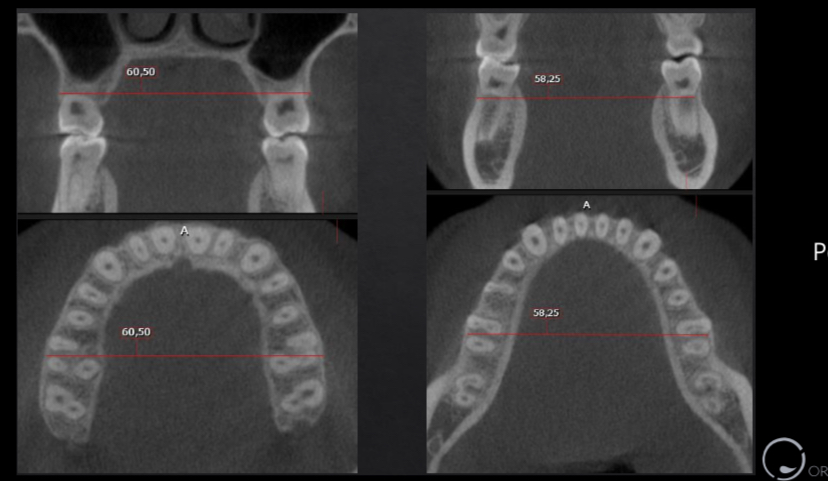

Sideways Expansion in Orthodontics - Clonmel Orthodontics

Sideways Expansion in Orthodontics At Clonmel Orthodontics we use cutting edge technology and state of the art equipment. Dr John Buckley is both Clonmel's most qualified and most experienced orthodontist.